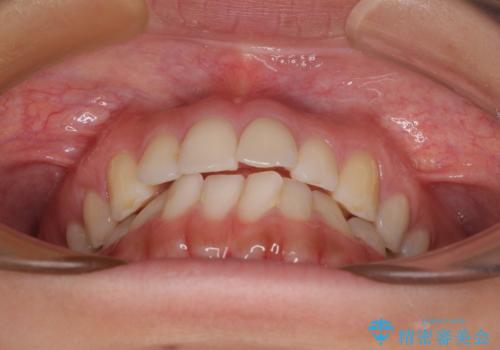

前歯の重なりをインビザライン・モデレートで矯正治療

- 上下前歯の重なりを気にして来院された患者様です。

安価なインビザラインパッケージを用いての治療を希望されており、デコボコの程度が中等度であったため、インビザライン・モデレートを用いて矯正治療を行うこととしました。